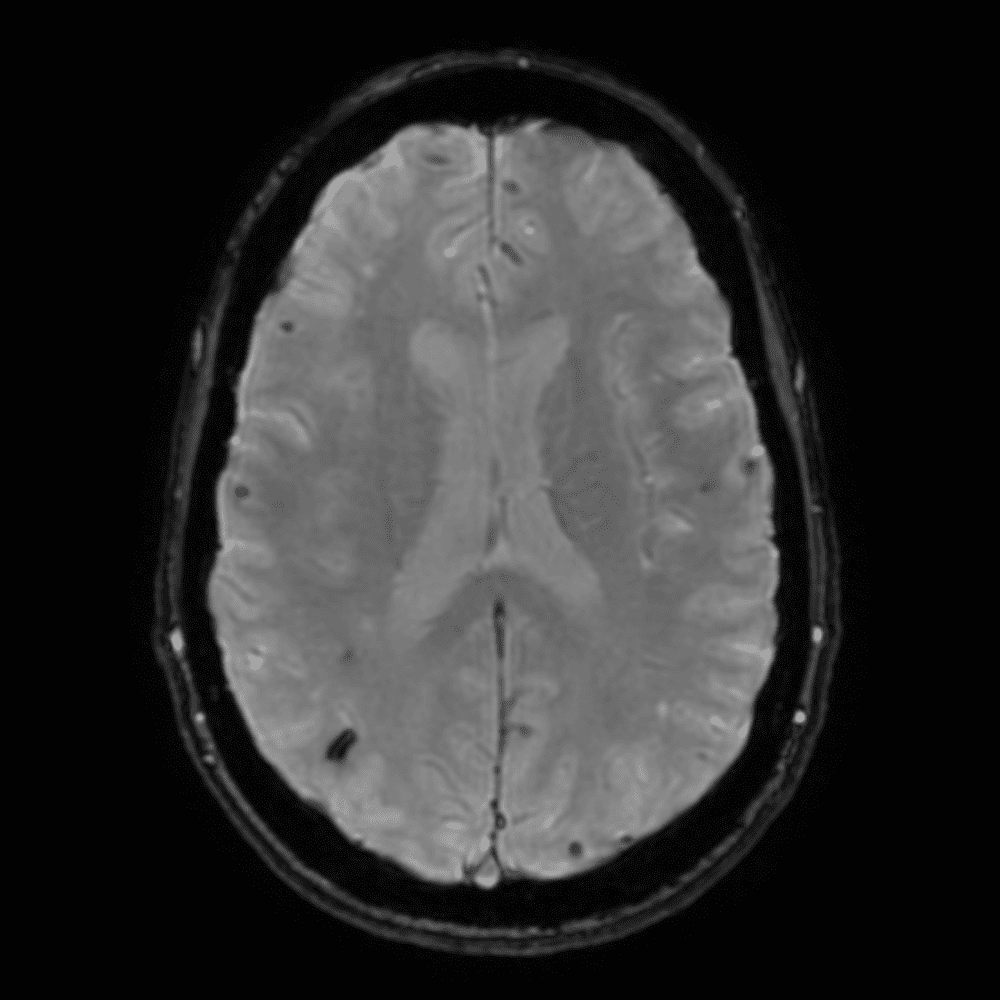

๋‹น์ง ์‹œ ํ”ํžˆ ๋ณผ ์ˆ˜ ์žˆ๋Š” ์‚ฌ๋ก€์˜ ์ „ํ˜•์ ์ธ ์˜ˆ๋ฅผ ํฌํ•จํ•ฉ๋‹ˆ๋‹ค.

39 ์‚ฌ๋ก€

์—ฐ์Šต

๋ฏธ๋ฌ˜ํ•˜๊ฑฐ๋‚˜ ์–ด๋ ค์šด ์‚ฌ๋ก€์™€ ์ผ๋ถ€ ์ •์ƒ ์‚ฌ๋ก€๋ฅผ ํฌํ•จํ•˜์—ฌ ๋‹น์ง์„ ์‹œ๋ฎฌ๋ ˆ์ด์…˜ํ•ฉ๋‹ˆ๋‹ค.

50 ์‚ฌ๋ก€